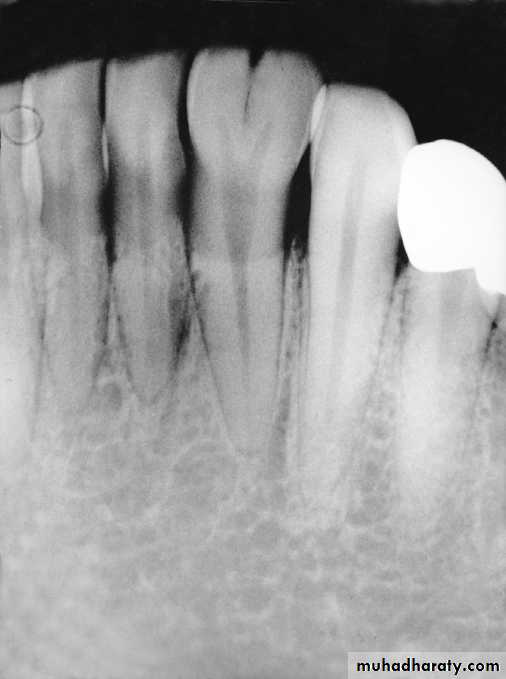

Patient’ age nearly 9 because the lower canines erupted and their eruption on 9-10 year and the upper lateral emerging now

This child is 7-8 years old because he has the upper maxillar centrals erupted (depending on schedule of time of eruption of permanent teeth (eruption lecture)